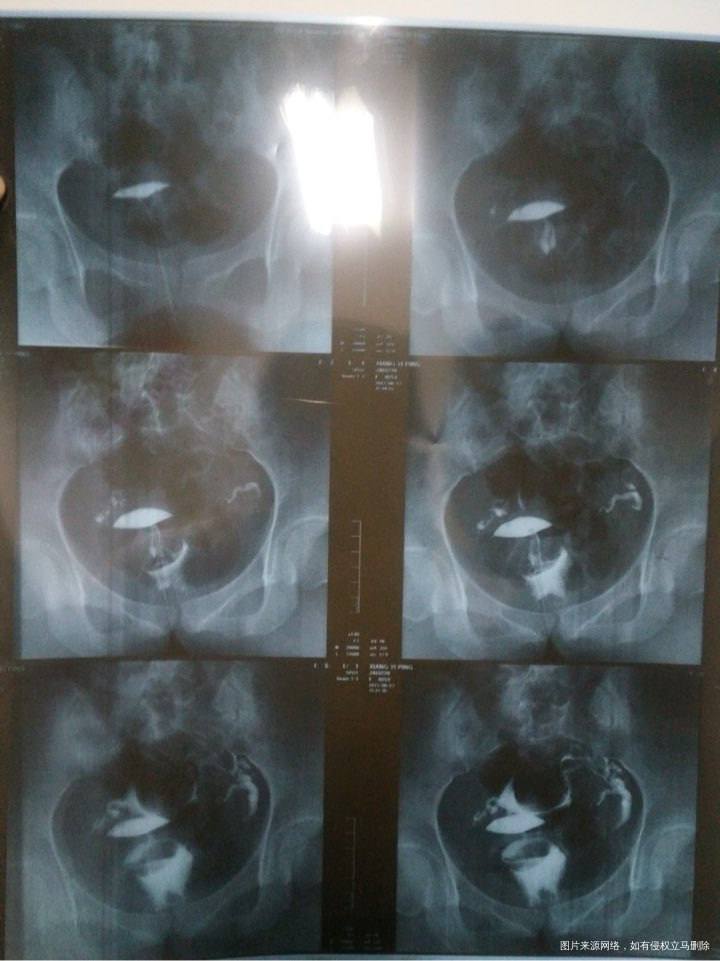

有医生在不、麻烦帮我看看我输卵管造影,严重不、自然受孕几率大不、需要怎样治疗